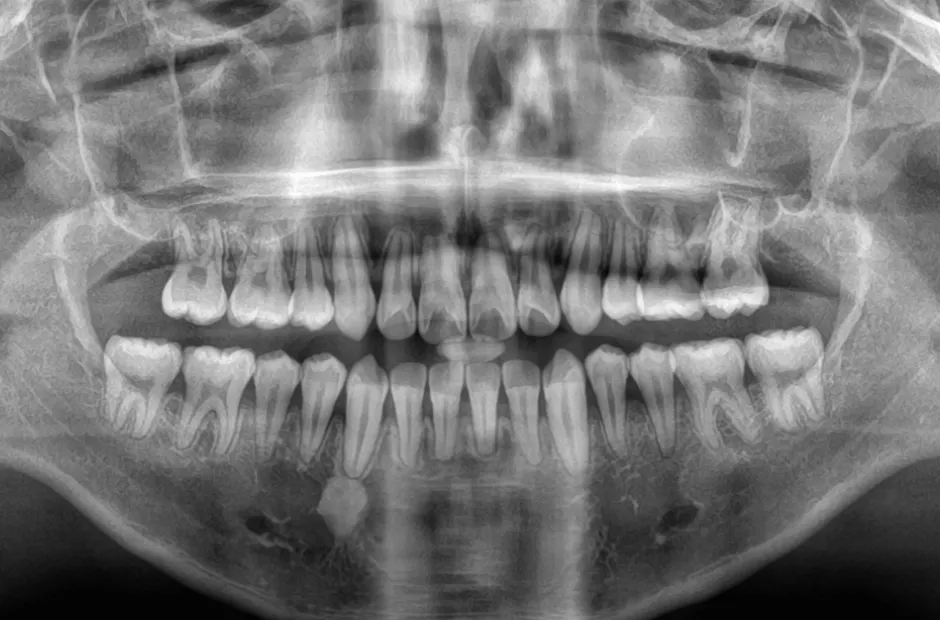

治療後